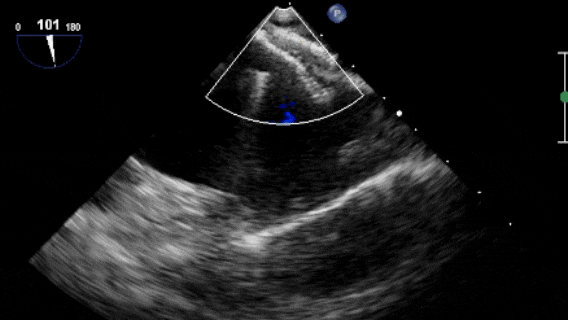

沿加硬導絲將9F輸送鞘送至左心房,退出導絲及輸送鞘內芯后,在超聲引導下送入1824PFO封堵器進行封堵。先釋放左盤面,整體回撤,緊貼房間隔,后釋放右盤面,進行推拉試驗,超聲在主動脈短軸切面、四腔心切面確認封堵器對二尖瓣等周圍組織無影響,位置及形態良好后釋放封堵器。撤出長鞘、縫合穿刺點后壓迫止血,加壓繃帶包扎,手術結束。

釋放左盤面及腰部

釋放右盤面

牽拉試驗

超聲觀察對周圍組織無影響